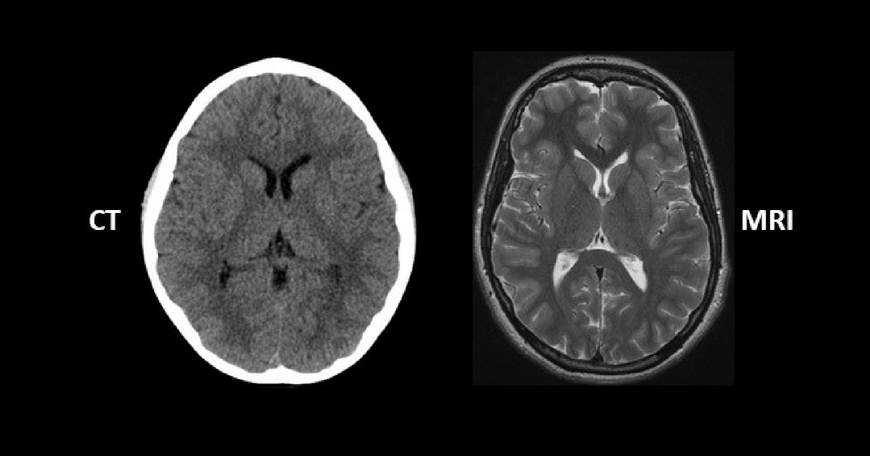

RM dhe TK janë metoda diagnostike në radiologji që përdoren për të zbuluar probleme të ndyshme në brendësi të trupit, edhe atë plotësishtë në mënyrë joinvazive. Zakonisht për: tumoret, frakturat, patologjitë e ndryshme të indeve të buta, gjakderdhjet, sëmundjet e enëve të gjakut, infeksionet apo lëndimet. Për të përcaktuar llojin e metodës diagnostifikuse është e rëndësishme të dihet se çka kërkohet të vizualizohet dhe arsyen për të cilen duhet të bëhet ky ekzaminim.

- Rezonanca magnetike – është procedurë pa dhimbje. Procedura mund të përsëritet aq sa është e nevojshme duke mos shkaktuar efekte anësore përshkak se nuk përdoren rrezet X. RM punon mbi principin e fushës magnetike, dhe si e tillë, nuk preferohet për persona të cilet kanë implante metalike, klipse të ndryshme kirurgjikale ose PaceMaker. Poashtu personave klaustofobik (fobi nga hapësirat e mbyllura), paraprakisht iu jepet anestetik, nga fakti se pacienti gjatë ekzaminimit të një RM futet në brendësinë e një cilindri të madh.

- Tomografia e Kompjuterizuar – është procedurë pa dhimbje. Procedura rekomandohet vetëm për arsye të forta mjekësore përshkak se punon me rrezatim jonizues (doza efektive e rrezatimit nga ky ekzaminim është rreth 10mSv, e njëjtë me vlerën mesatare të rrezatimit që një person merr në tre vjet nga rrezatimi diellor). CT nuk rekomandohet për gratë shtatzëna për shkak të rrezikut të madh që ka tek fetusi.